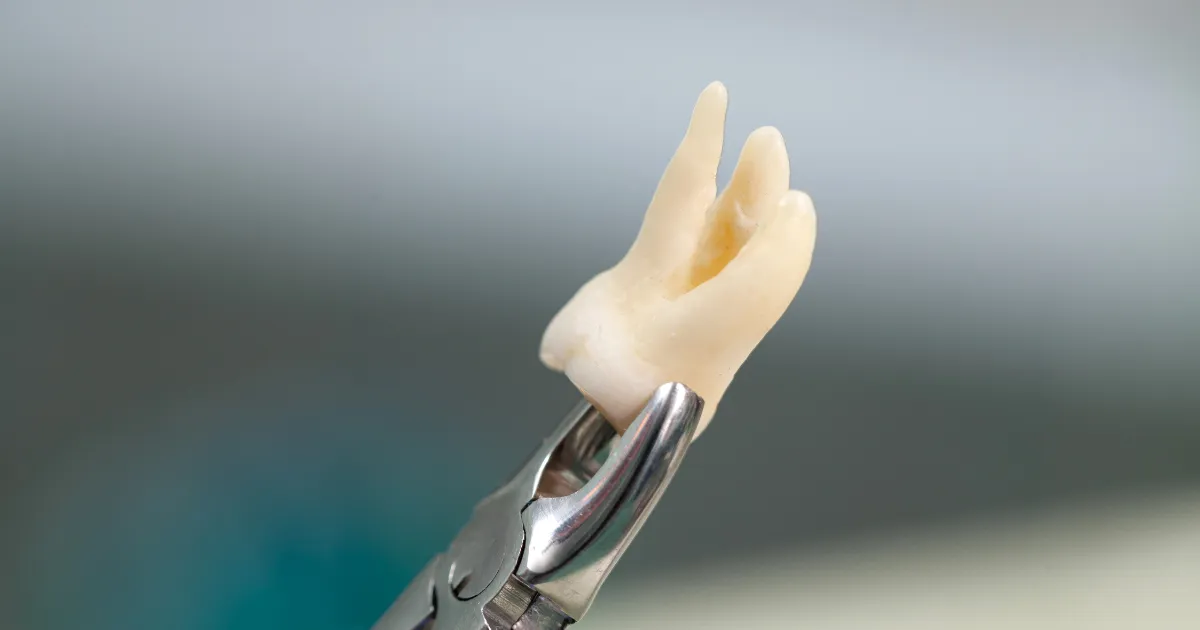

親知らずの抜歯は、埋まっている位置や神経との関係によっては難易度が高くなることがあります。

事前にレントゲンやCTスキャンを使い、親知らずの位置や神経との関係を詳細に診断します。